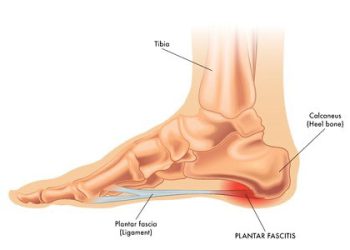

خار پاشنه ممکن است در بسیاری از افراد به وجود آید اما آنها هیچ وقت متوجهاش نشوند؛ زیرا هیچ علائمیدر...